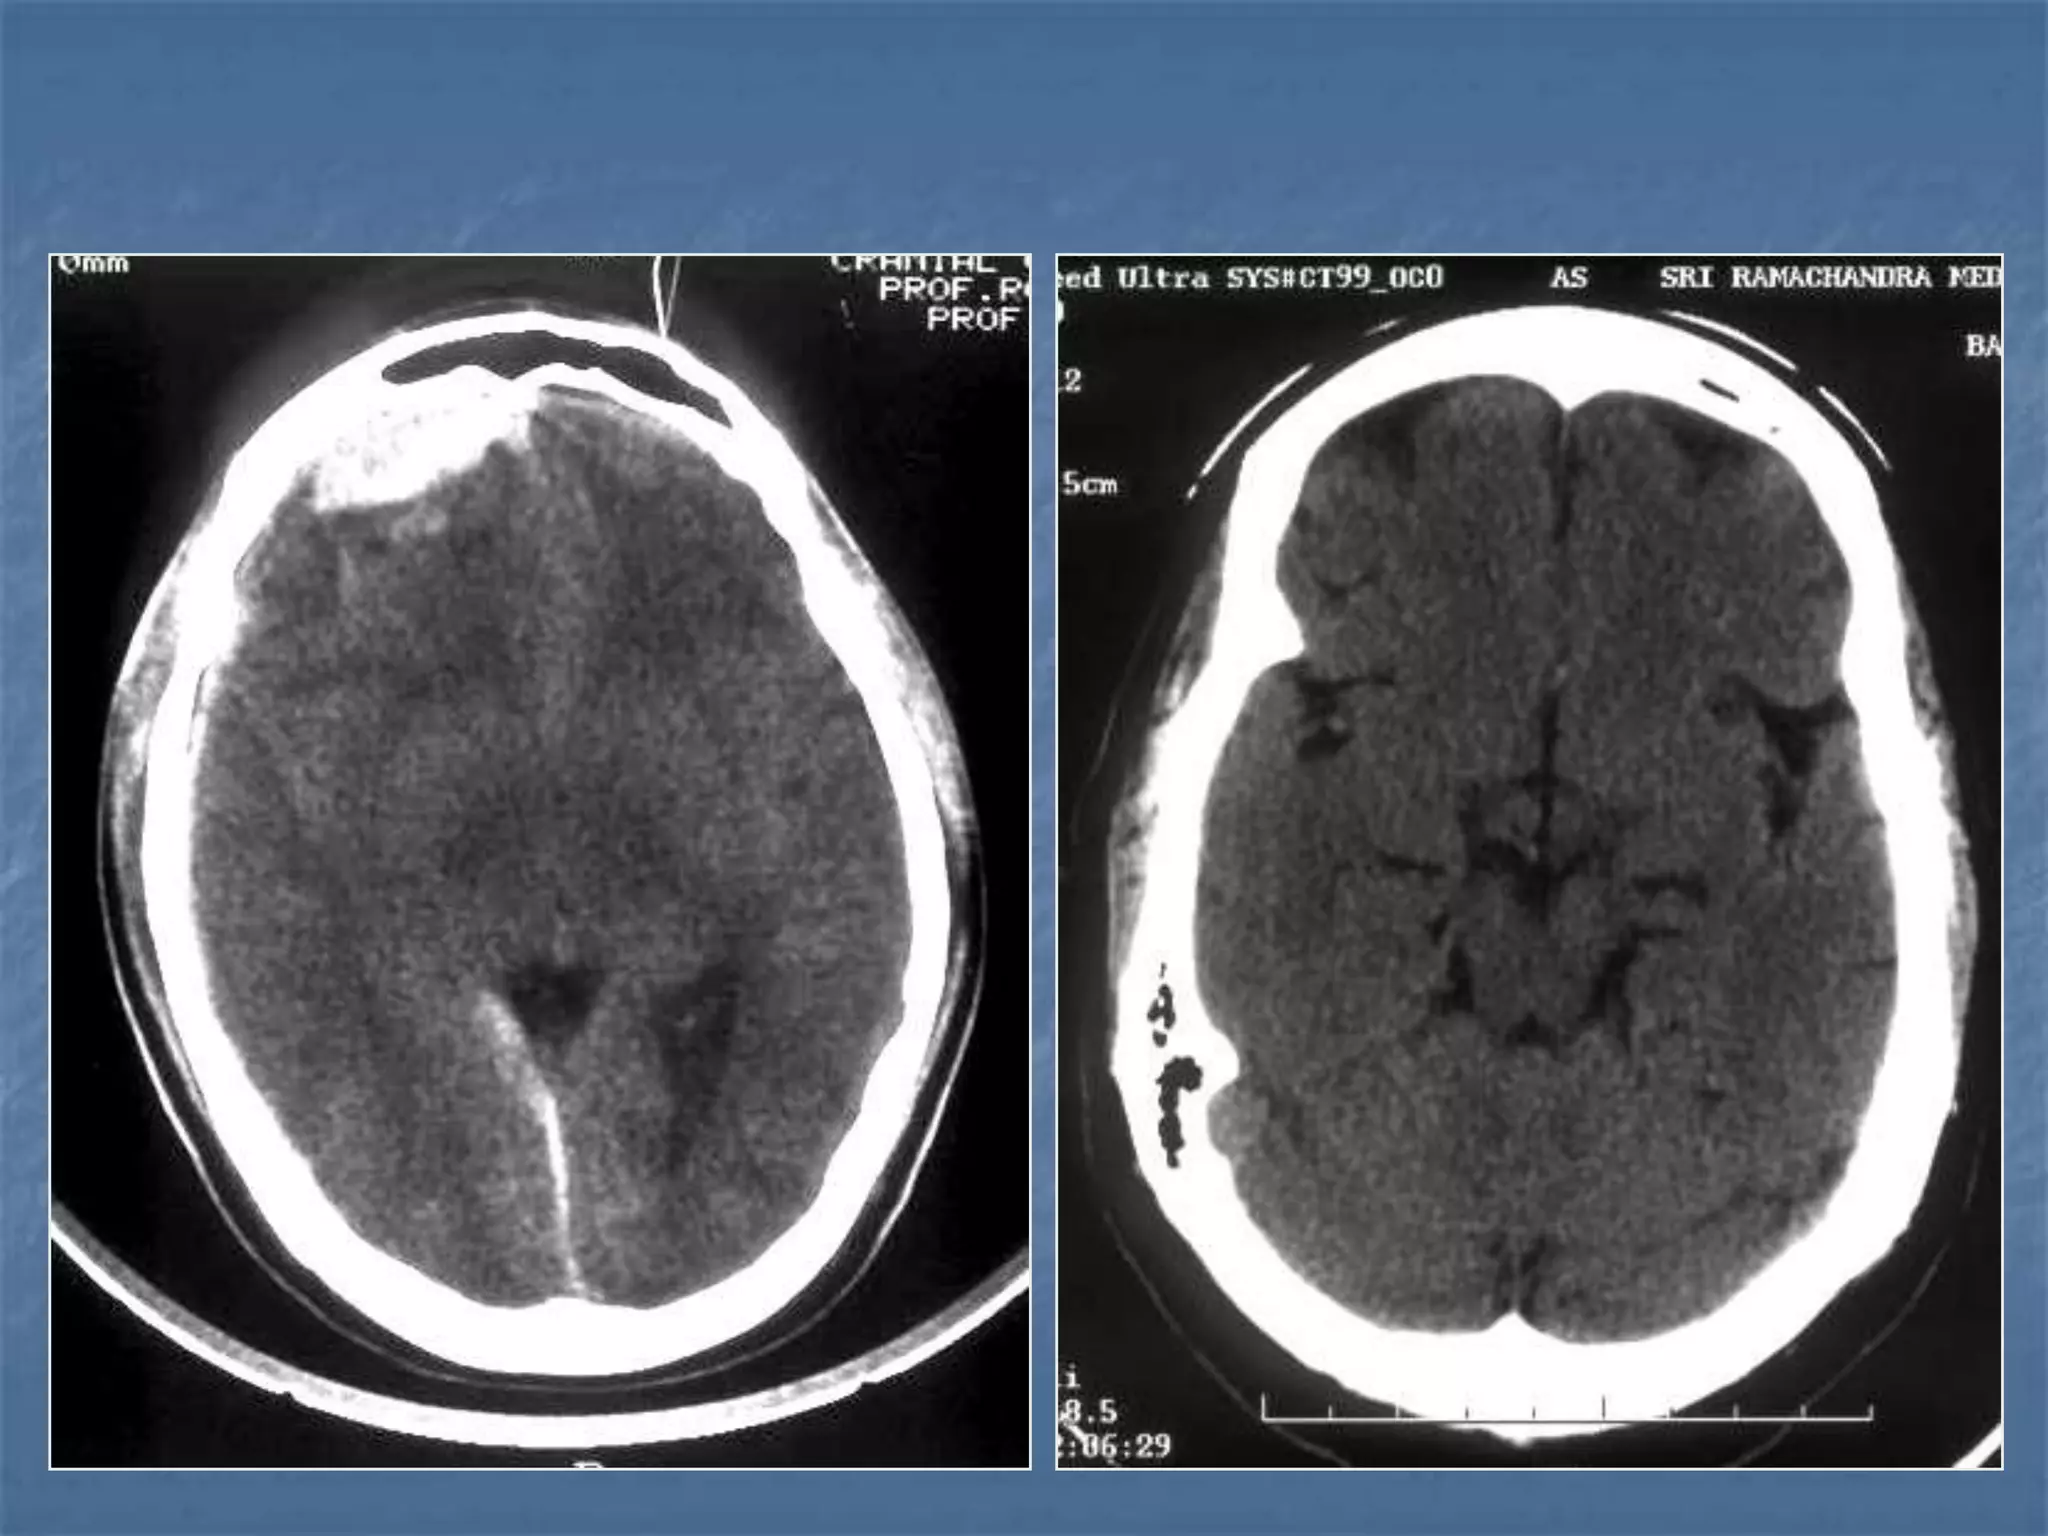

SUBACUTE SDH

ACUTE ON CHRONIC SDH

CONTUSION SAH